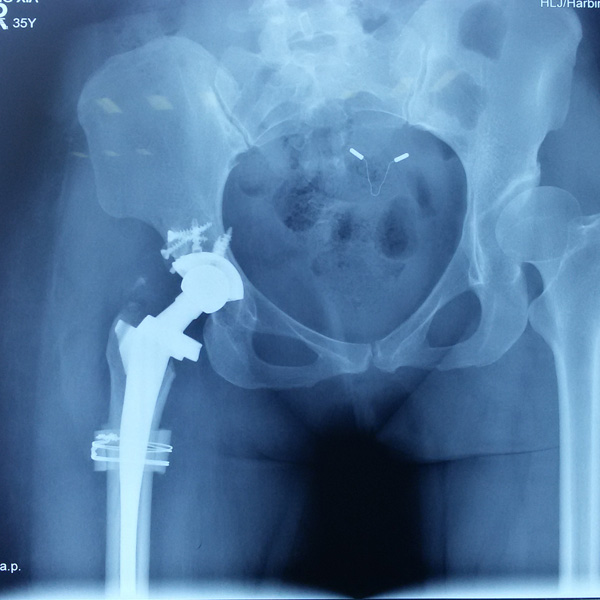

• 骨肉瘤手術骨肉瘤手術手術后手術前

骨肉瘤手術

患者張某,女,14歲,診斷為“左股骨遠端骨肉瘤”,當地醫院因為醫療技術和能力的限制,只能考慮截肢手術。患者家屬通過平臺推薦,指定到哈......